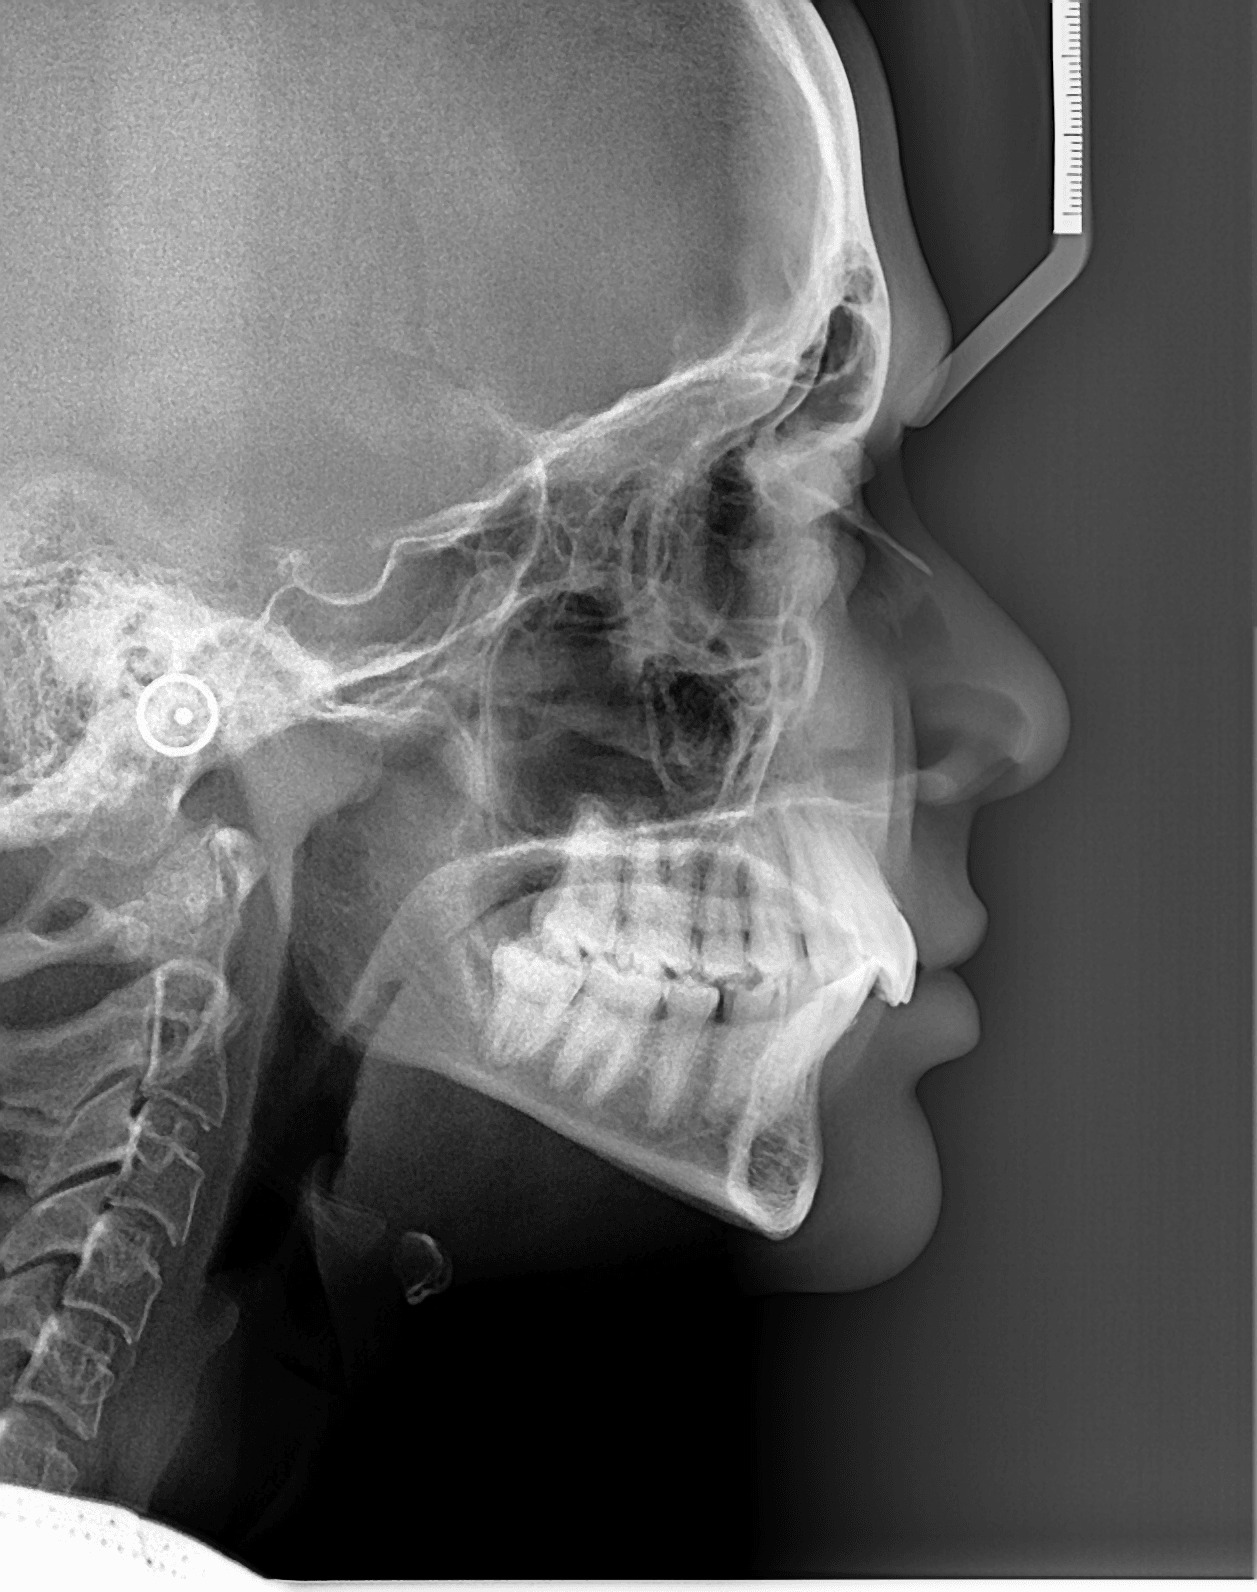

Телерентгенография (CEPH)

Телерентгенографията е профилна снимка на черепа. Обикновено се прави на деца за нуждите на ортодонтията. По нея лекарите измерват и анализират захапката, планират необходимите корекции и проследяват развитието на челюстите и зъбите.